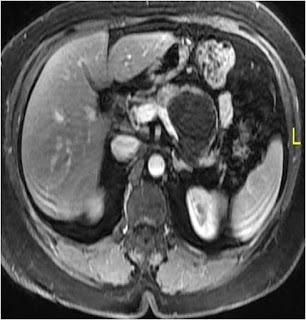

The patient was further investigated with contrast enhanced abdominal magnetic resonance imaging (MRI) of the abdomen which showed a well defined, large (> 5 cm) unilocular cystic lesion with thick enhancing capsule located centrally in the body of pancreas. There was no duct – cyst communication (Figure 1 & 2).

Figure 1